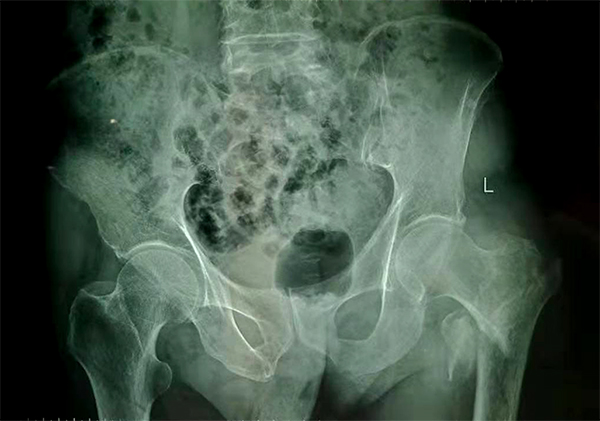

經(jīng)檢查拍片診斷為左股骨粗隆間粉碎性骨折,收入骨科住院,張爺爺既往有“2型糖尿病”病史10余年,還有“腦梗塞”病史5年,導(dǎo)致左側(cè)肢體偏癱。

手術(shù)前